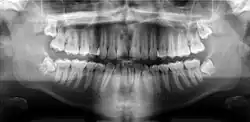

Panoramic radiograph

A dental panoramic radiograph, showing the maxilla and mandible, all the teeth including the "wisdom teeth," the frontal and maxillary sinuses, the nasal cavity and the temporomandibular joint and other near by head and neck anatomy. | |

A panoramic radiograph is a panoramic scanning dental X-ray of the upper and lower jaw. It shows a two-dimensional view of a half-circle from ear to ear. Panoramic radiography is a form of focal plane tomography; thus, images of multiple planes are taken to make up the composite panoramic image, where the maxilla and mandible are in the focal trough and the structures that are superficial and deep to the trough are blurred.